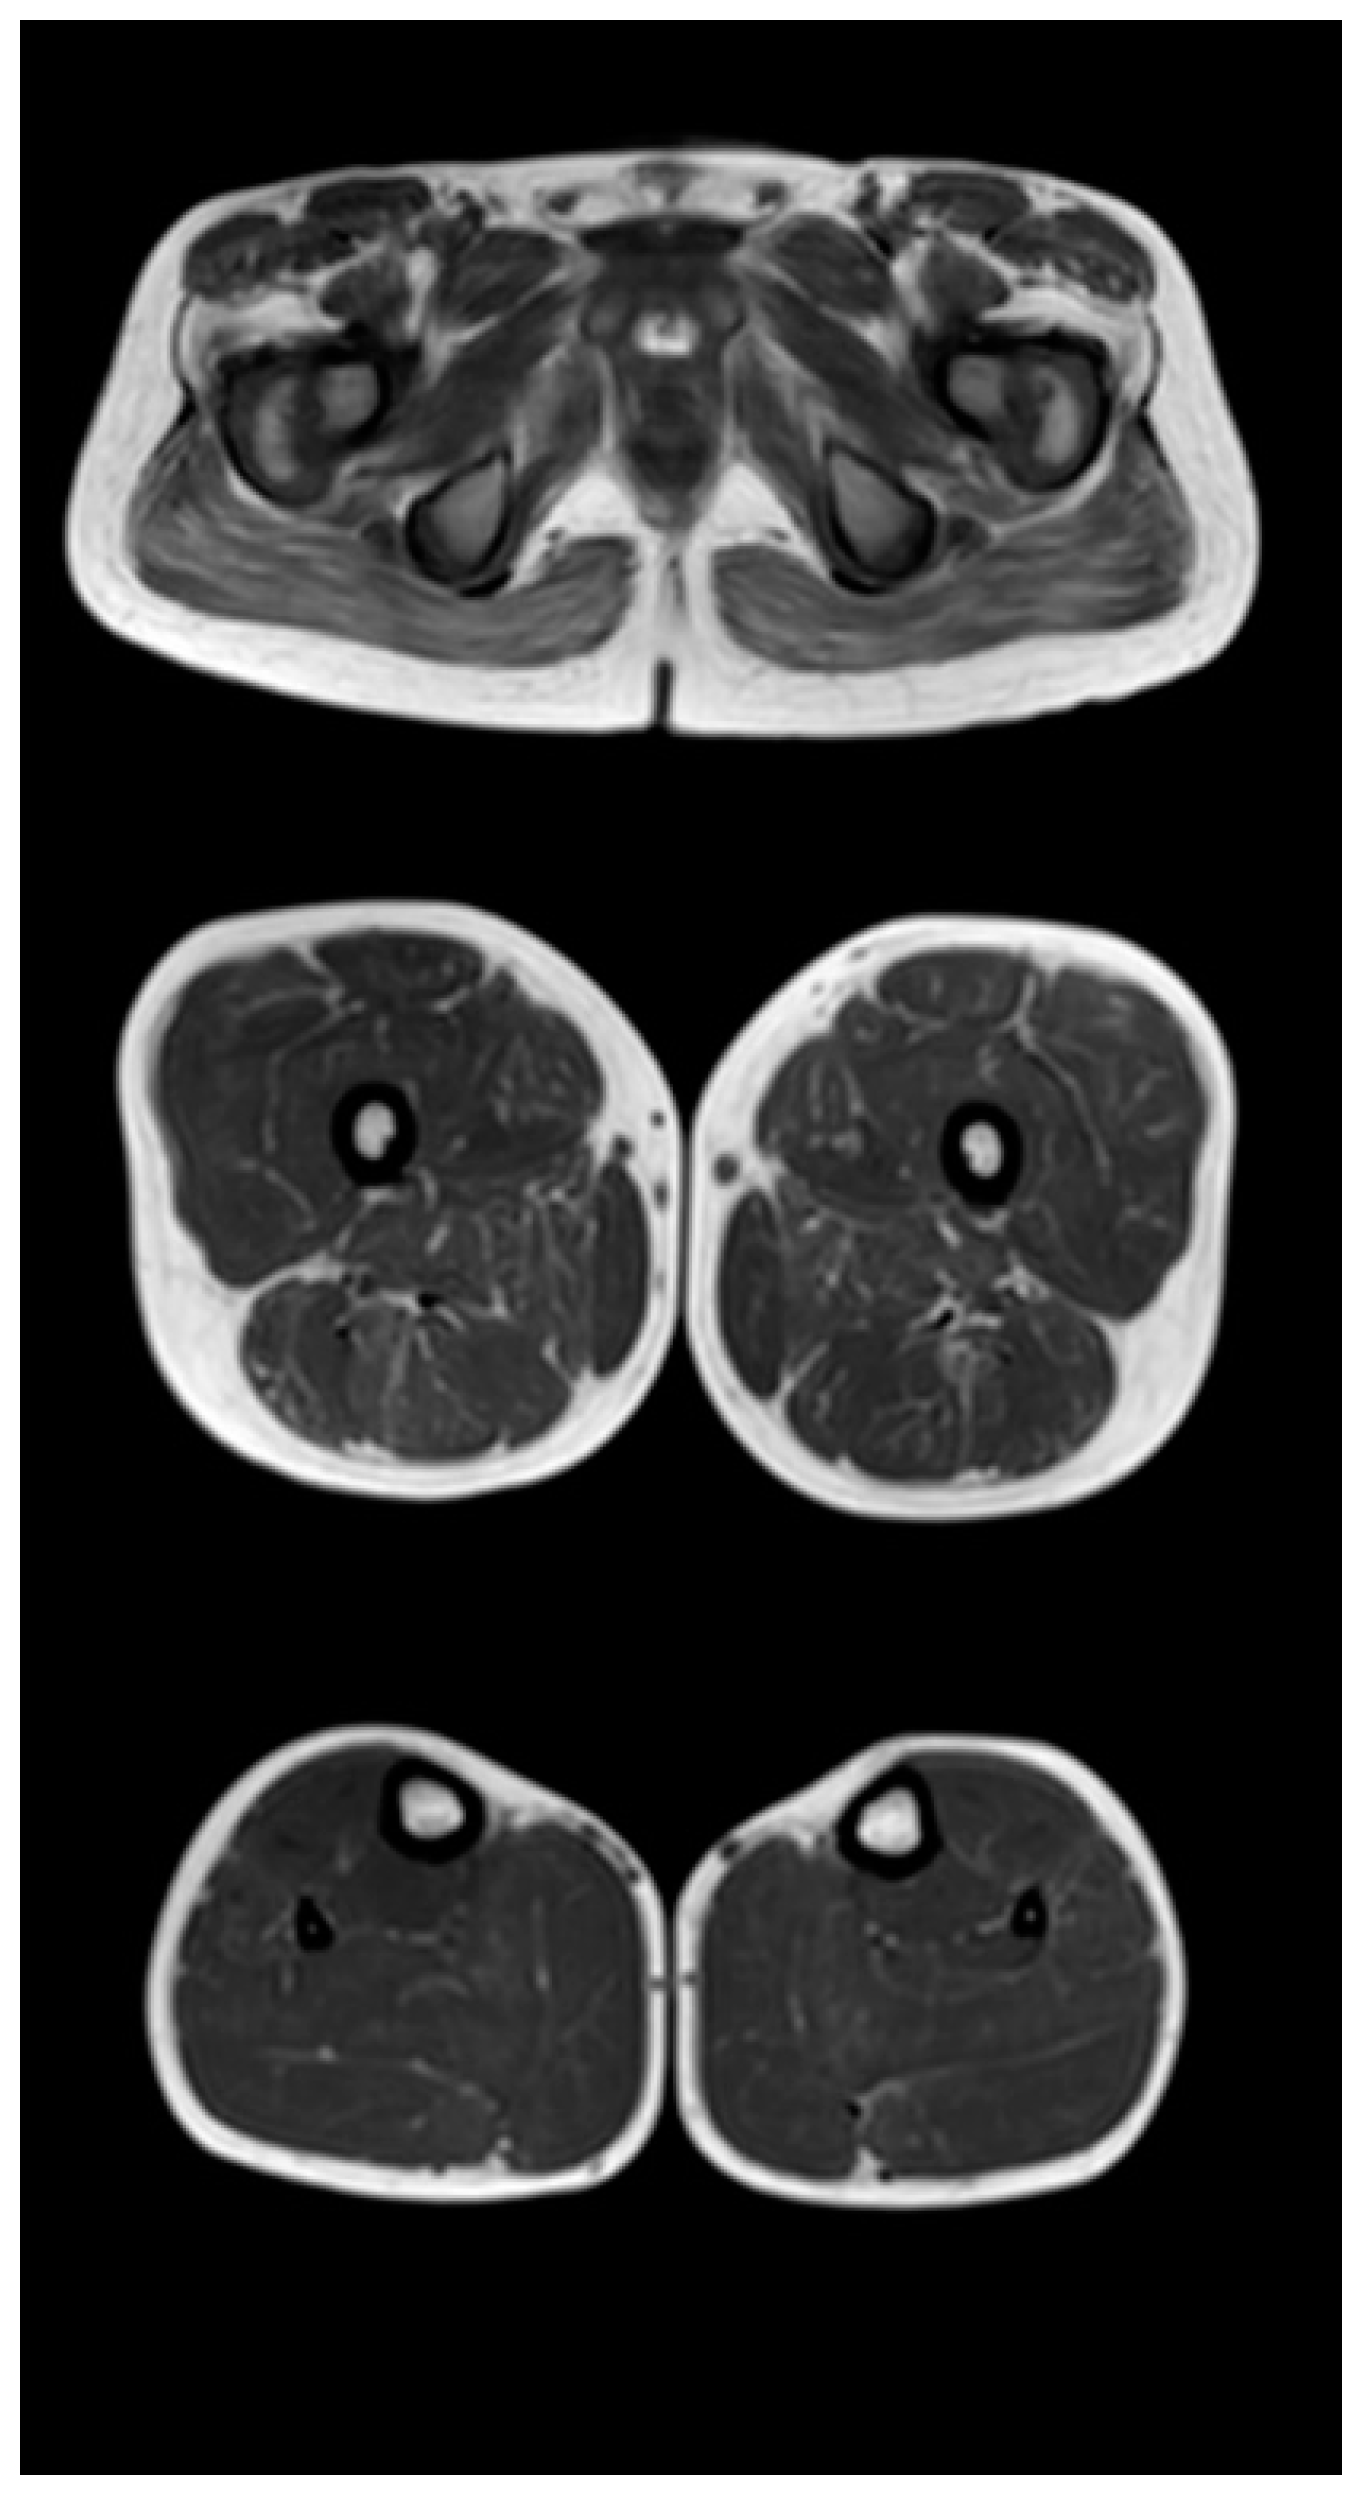

Figure 3, Figure 4 and Figure 5 show the main changes in the muscles at different stages of the disease. The muscles of the pelvic girdle are characterized by early symmetric fibro-fatty degeneration of the gluteus maximus muscles, in the Figure characterized by stage 2b on the Mercuri scale. In the hips, the early lesion pattern is characterized by primary involvement of the adductor mausors (stage 2a). It is also characterized by slight diffuse changes in the quadriceps muscles and the posterior group of muscles of the thighs. In the muscles of the legs at the early outpatient stage, nonspecific diffuse muscle fat substitution is characteristic of stage 1 (Figure 3).

Figure 3.

Pattern of involvement of the muscles of the lower extremities in a patient at an early outpatient stage of the disease (6.1 years). From top to bottom: the pelvic level, the femoral level, and the level of the legs.